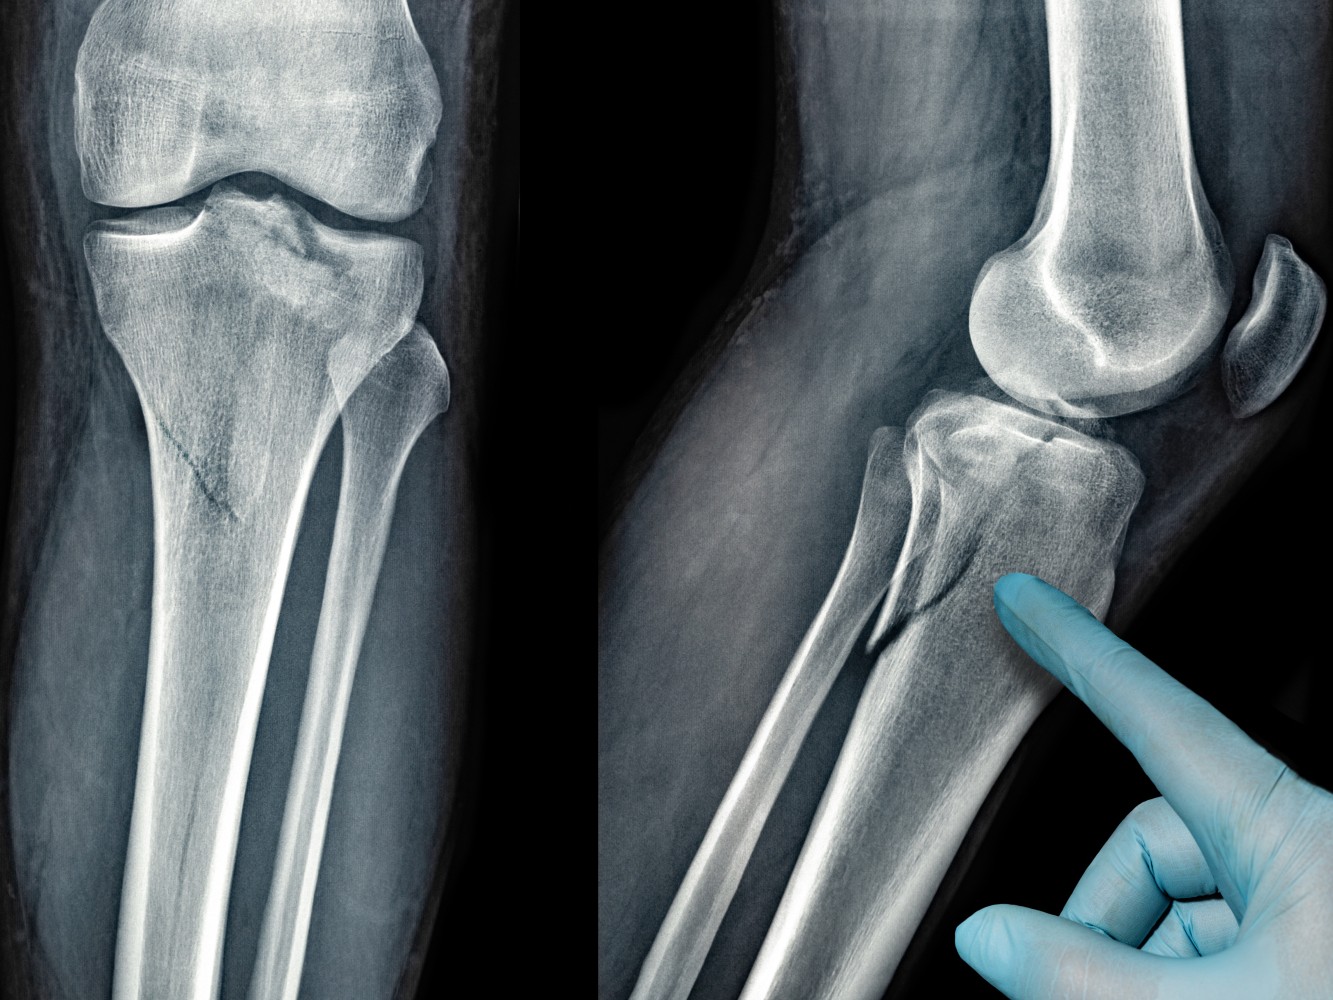

Complex Fracture Treatment

He has completed MBBS and MS in Orthopaedics, followed by specialized fellowships in Advanced Trauma, Robotic & Conventional Joint Replacement, and Arthroscopy. His clinical expertise spans adult and pediatric trauma, fracture management, joint replacement surgeries, sports injuries, and spine-related conditions.

Dr. Anmol has treated 2000+ patients and has been involved in 500+ orthopaedic surgeries, including complex trauma cases and advanced joint replacement procedures. His exposure to robotic joint replacement and arthroscopy allows him to offer precise, minimally invasive solutions with faster recovery and improved outcomes.